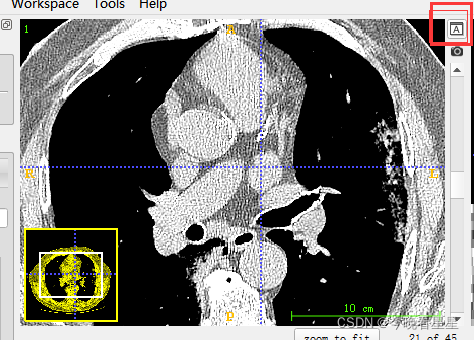

显示一个主图

- 对当前进行截图